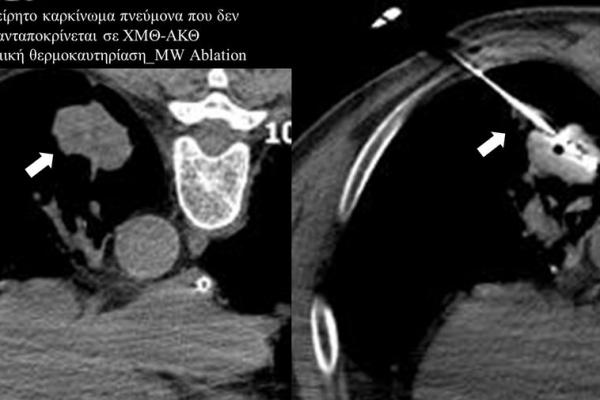

Πρόκειται για την πιο σύγχρονη τοπική θεραπεία όγκων του ήπατος, του νεφρού, του πνεύμονα, των οστών και των όγκων μαλακών μορίων. Παθοφυσιολογικά βασίζεται στην τοπική καταστροφή των καρκινικών κυττάρων με τη δημιουργία ιδιαίτερα υψηλών θερμοκρασιών εντός του όγκου. Αυτό επιτυγχάνεται με τοποθέτηση ειδικών ηλεκτροδίων εντός του όγκου υπό ακτινολογική καθοδήγηση (αξονικός τομογράφος ή υπέρηχος). Τα ηλεκτρόδια αυτά παράγουν υψηλή θερμοκρασία είτε με τη βοήθεια ραδιοσυχνοτήτων (RFablation), είτε με τη βοήθεια μικροκυμάτων (MWablation) και προκαλούν πηκτική νέκρωση των καρκινικών κυττάρων χωρίς να επηρεάζουν τα φυσιολογικά κύτταρα.Το αποτέλεσμα είναι μόνιμο.